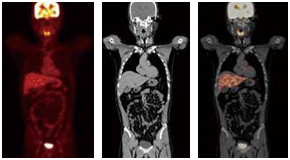

간은 인체에서 가장 큰 장기 중 하나로, 여러 가지 중요한 기능을 수행합니다. 간 질환은 매우 일반적인 문제로, 신속하고 정확한 진단이 필요합니다. 복부 CT를 통해 간의 경화, 종양, 지방간 등 다양한 문제를 확인할 수 있습니다. 특히 간암의 경우, CT 촬영은 초기 단계에서 종양의 크기와 위치를 평가하는 데 중요한 역할을 합니다. CT 이미지는 간 내 혈관과 주변 조직의 상태를 상세히 보여주기 때문에, 간암이 다른 장기로 전이되었는지 파악하는 데도 유용합니다.

간암은 조기 증상이 거의 없기 때문에 진단이 늦어지는 경우가 많습니다. 그러나 복부 CT를 통해 초기 증상을 발견할 수 있다면, 치료 옵션이 훨씬 다양해집니다. 간암의 원인으로는 간염 바이러스 감염, 알코올 남용, 비만 등이 있으며, 이들 요인을 관리함으로써 예방할 수 있습니다. CT 촬영을 통해 조기에 간암을 발견하면, 간 절제술이나 간 이식과 같은 치료를 통해 생존율을 높일 수 있습니다.